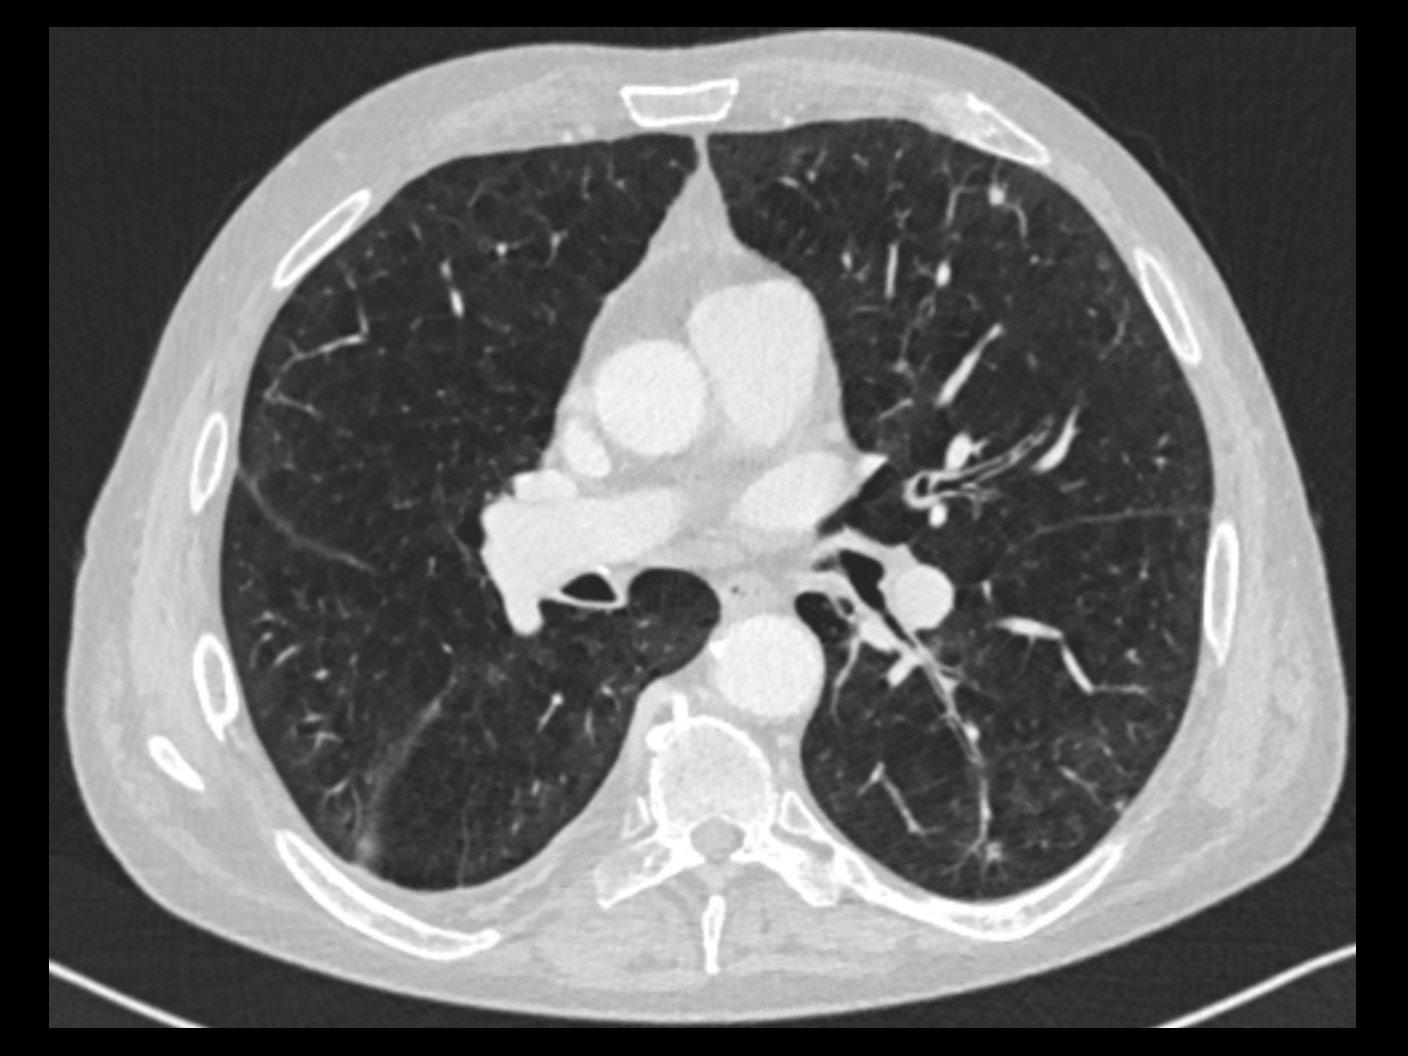

With a mobile lung cancer screening program, you can bring the low-dose CT exam that at-risk patients need closer to where they live. With a short set-up, our self-contained Mobile Lung Screening Solution with a SOMATOM go.Up CT scanner offers the high image quality, ease of use, and flexibility you need to create a lung screening program that meets the real-life needs of your community.